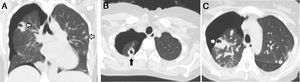

We report the case of a 41-year-old woman with a history of kidney transplantation with chronic graft dysfunction, who was undergoing hemodialysis 3-times-weekly via temporary jugular catheter. The patient was admitted with a diagnosis of catheter sepsis with positive blood cultures for methicillin-resistant Staphylococcus aureus. She developed sudden dyspnea and chest pain 72h after admission. A chest computed tomography was performed that showed right pneumothorax associated with cavitary pulmonary nodules (Fig. 1), some of which were peripheral. A diagnosis of spontaneous pneumothorax following rupture of septic cavitary emboli in the pleural space was established. The pneumothorax was treated with pleural drainage for 4 days. A 4-week course of antibiotic therapy with vancomycin was indicated, with good clinical progress.

Catheter-associated infection is a frequent cause of septic pulmonary embolism.1 The causative microorganism is usually Staphylococcus aureus. Lesions are cavitary in 56% of cases1 and, when they occur in a peripheral site, they can open to the pleural space, triggering secondary spontaneous pneumothorax.2 This complication is rare and usually occurs between 5 and 15 days after starting antibiotic treatment.2